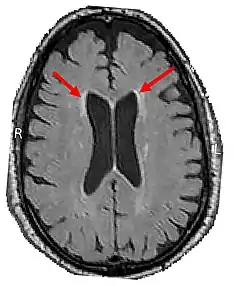

LENAS is seen with damage to the white matter and axons within the brain. The external human LENAS brain shows findings in several major structures. There is mild atrophy of the frontoparietal regions of the brain and a mild reduction of the thalamus and rostral (front) part of the caudate nucleus (which is located in an area of the brain called the basal ganglia).[4] Abnormalities in the frontal, frontoparietal, and temporal lobes are most severe and predominant with LENAS and asymmetry of the cerebral hemispheres has sometimes been found.[4] LENAS also may show moderately enlarged lateral ventricles and atrophy in corticospinal tracts as well as in the pons.[4]

The area where it is seen to be the most pronounced abnormalities appear in the white matter below the pre- and postcentral gyri that extend through the posterior limb of the internal capsule into pyramidal tracts of the brain stem.[4]